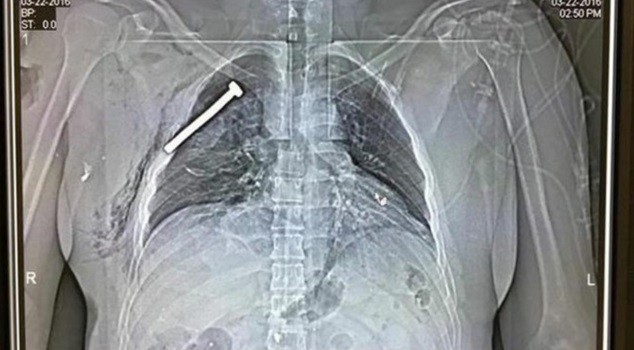

▲院方在部分傷者身上發現許多釘子。(圖/翻攝自Hartvannederland)

比利時首都布魯塞爾爆發連環恐攻,造成35人死亡、超過百人受傷,歐洲各國再度陷入恐怖攻擊的陰影。當地北部醫院「University Hospital Gasthuisberg」今日公布傷者X光照,從畫面可見一根釘子直直插入胸腔。

據《鏡報》報導,醫院發言人馬克(Marc Decramer)表示,在部分傷者身上發現許多釘子,顯然是恐怖攻擊份子在炸彈內置入釘子,想藉此增加殺傷力,導致攻擊事件更加嚴重、傷亡人數不斷攀高。